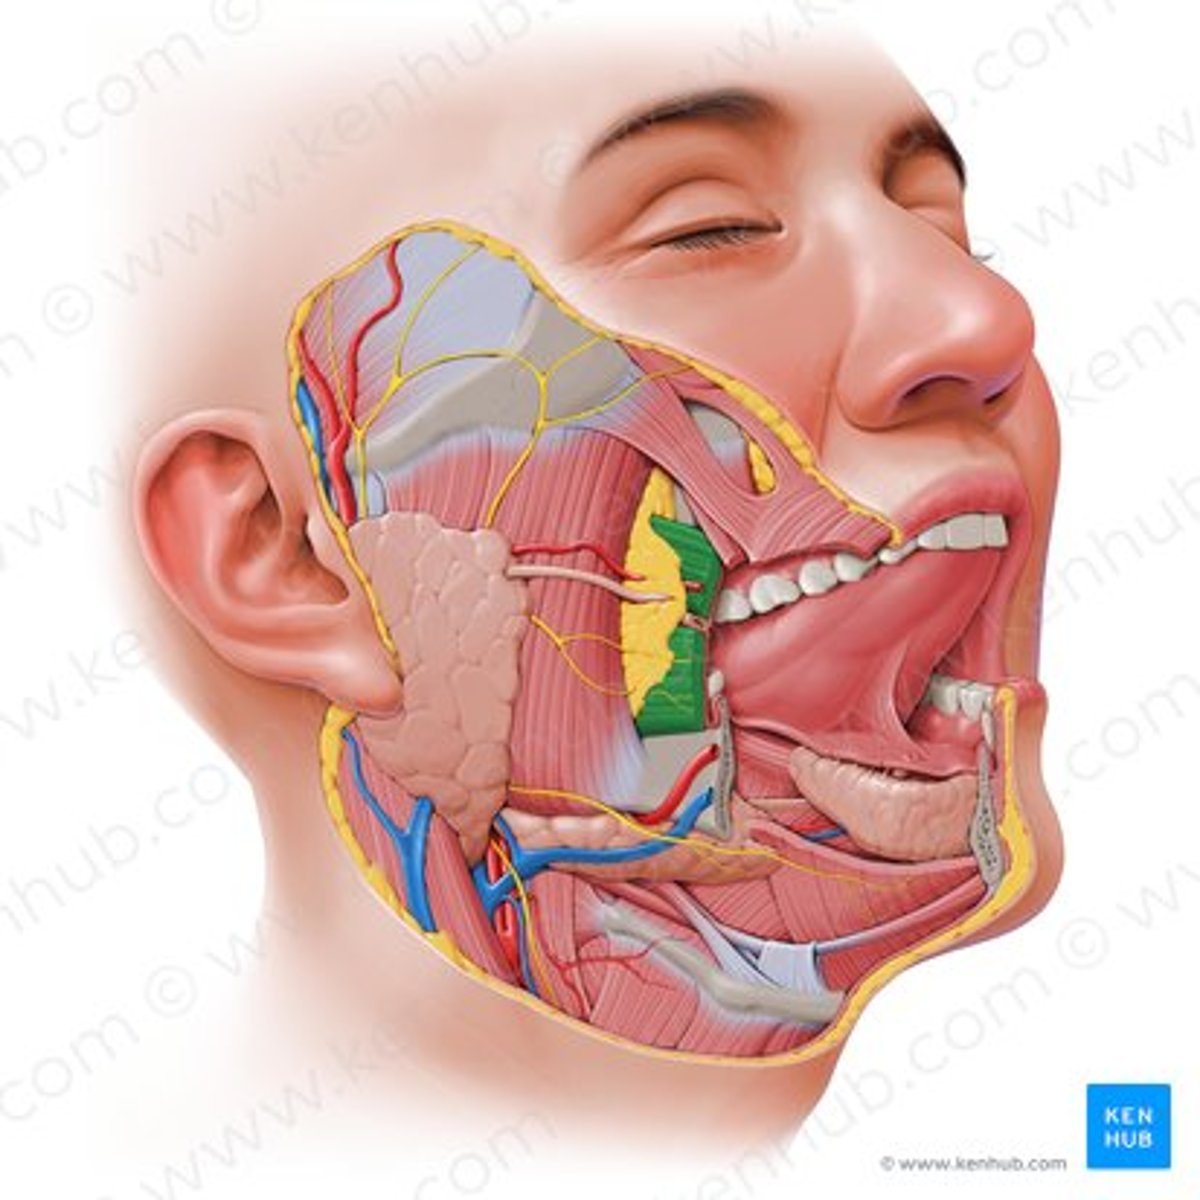

deep masseter

superficial masseter

temporalis

temporomandibular joint capsule

lateral pterygoid

inferior alveolar nerve

inferior alveolar artery

medial pterygoid

mental nerve

lingual nerve

buccal artery

buccal nerve

mandibular foramen

buccinator